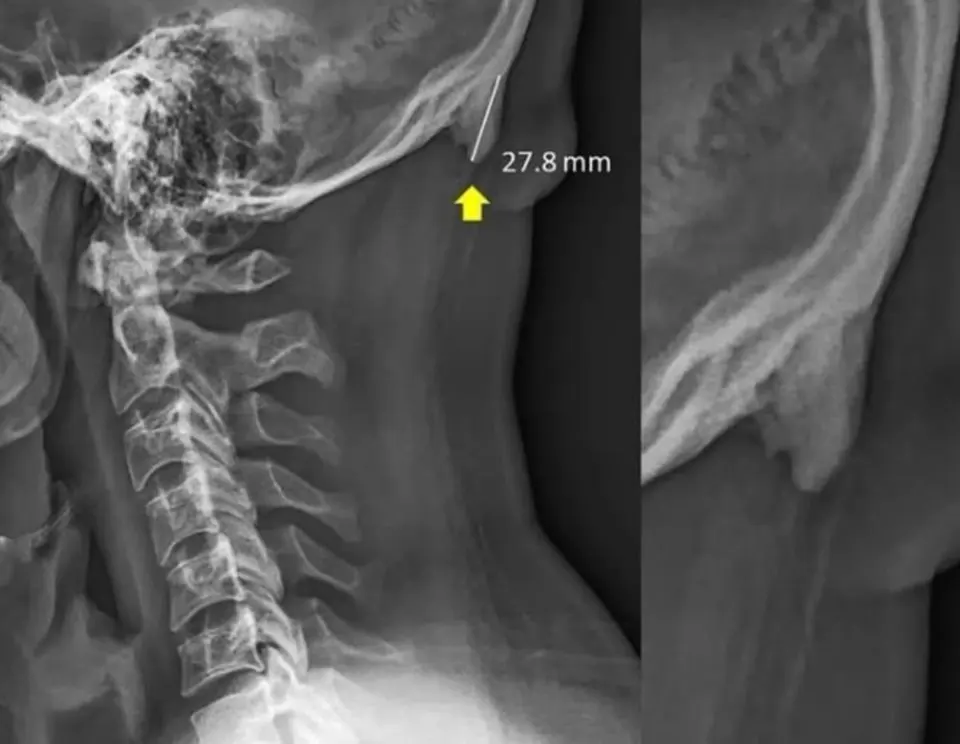

เป็นส่วนกระดูกที่งอกขึ้นมาเพิ่มตรงแถว ๆ ท้ายทอยยาวลงมาตั้งแต่ 5 มม. ไปจนถึง 30 มม. แล้วแต่ว่าใครยาวมากยาวน้อย

กระดูกส่วนที่งอกนี้ถูกเรียกโดยสื่อว่า “Head Horn” หรือ “Phone Horn” สาเหตุเพราะผู้วิจัยเชื่อว่าที่เขางอกออกมานี้ก็เพราะคนรุ่นใหม่ใช้มือถือเยอะ???

แต่เพราะลักษณะการโพสท่าเล่นมือถือที่ต้องก้มตลอดเวลา ทำให้กระดูกและกล้ามเนื้อคอไม่สามารถรับแรงได้ตามที่วิวัฒนาการดั้งเดิมออกแบบไว้ ก็เลยต้องงอกกระดูกมาตรงท้ายทอยเพื่อรับกับท่าทางใหม่

แต่ที่เจ๋งคือไม่ได้เกิดเคสสองเคส แต่ในผล X-Ray 1,200 ฟิล์ม พบเจอกระดูกที่งอกนี้ถึง 1 ใน 3 !

ส่วนใหญ่เป็นคนรุ่นเด็กไปจนถึงวัยรุ่น ส่วนคนอายุมากมีน้อยมาก (ปัจจัยหลักคืออายุและเ พ ศ)